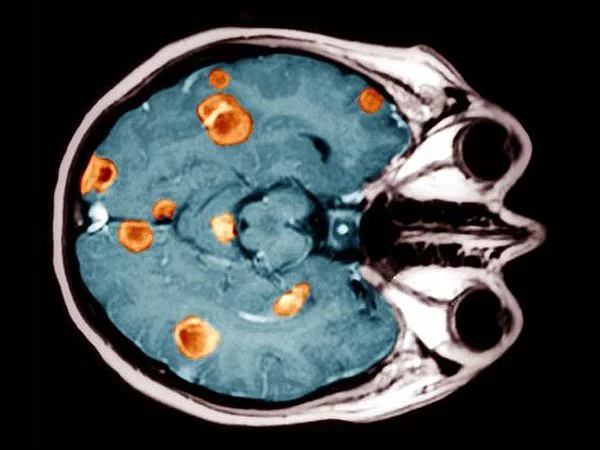

- Компьютерная и магнитно-резонансная томография. Для уточнения локализации или характера метастазов по всему организму, а также нахождения их в соседних органах.

- Позитронно-эмиссионная томография или ПЭТ-сканирование. Компьютерная томография с контрастным веществом. Оно накапливается в опухолевых и метастазовых очагах и при исследовании подсвечивает вредоносные клетки и новообразования.